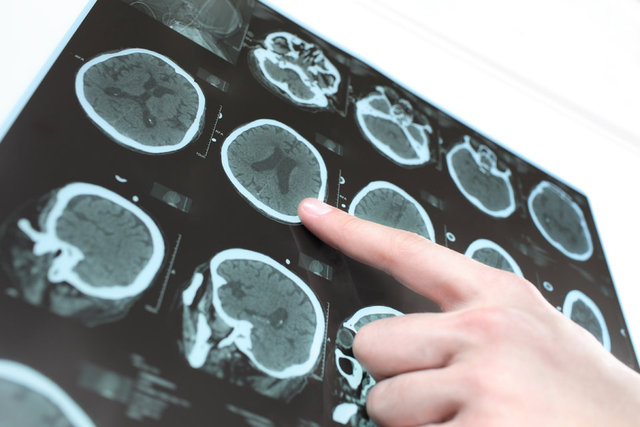

Beyin tümörünün 10 önemli belirtisi!

Beyin ve Sinir Cerrahisi Uzmanı Prof. Dr. Gökhan Bozkurt, beyin tümörlerinin belirtilerini şöyle sıraladı:

* Baş ağrısı,

* Baş ağrısına eşlik eden bulantı veya kusma,

* Bilinç kaybı ve bilinç düzeyinde bozukluklar,

* Daha önce hiç olmadığı halde nöbet (sara) geçirilmesi,

* Vücudun bir kısmında duyu veya kuvvet kaybı olması, uyuşukluk,

* Kısa zamanda gelişen görme kaybı, çift görme veya işitme kaybı,

* Hafıza ve davranış bozuklukları,

* Konuşma bozuklukları,

* Dengesizlik ve yürüme problemleri,

* Hormonal bozukluklar ve buna bağlı klinik semptomlar (erken ergenlik, el ve ayaklarda büyüme, adet döngüsü bozuklukları, hipertiroidi, kortizol yetmezliği veya fazlalığı…) yer almaktadır.